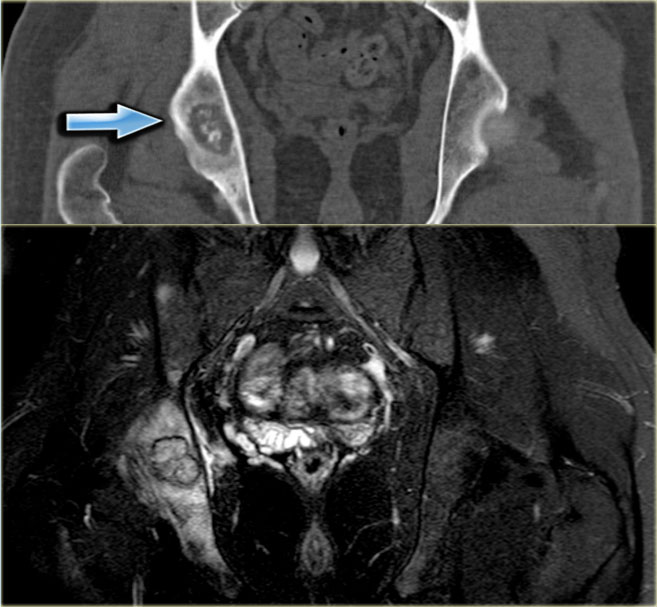

Here a patient with multiple osteochondromas.

Follow up is necessary because of an increased risk of malignant degeneration.

Continue with CT and MR.

CT:

• Large osteochondroma arising from the iliac bone.

• The central defect and punctate calcifications are highly suspicious for malignant progression to a peripheral chondrosarcoma.

MRI:

• The defect is filled with a large cartilage cap with high SI.

• This is diagnostic for the diagnosis chondrosarcoma